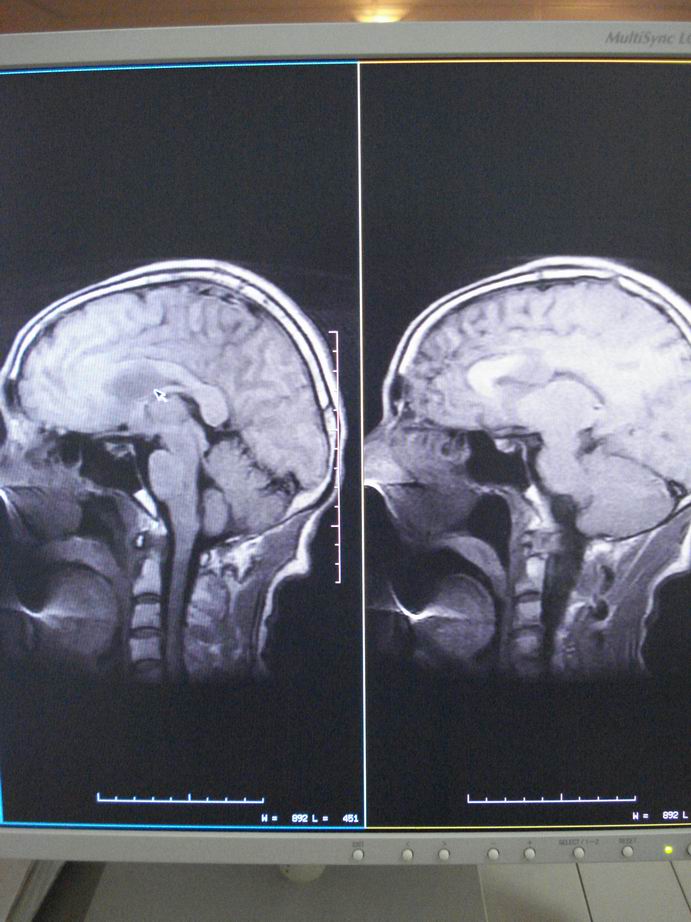

男60岁,左侧肢体乏力及精神异常10天,血压正常,血常规,肝肾功正常,腰穿无异常,请教颅内多发病灶,考虑什么?感染?肿瘤(转移性?)还是其它?

考虑为颅内多发转移瘤

脑内多发性转移瘤。

淋巴瘤较转移瘤可能大。